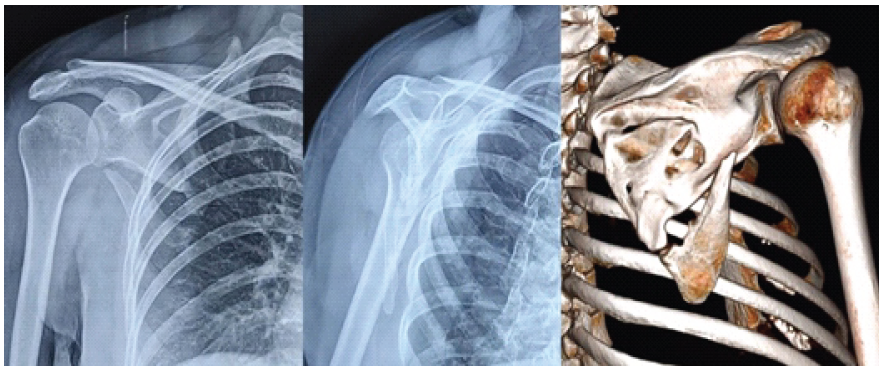

A 42-year-old right-hand-dominant female sustained a right scapular body fracture after a high-energy road-traffic accident. The patient was evaluated and stabilized according to Advanced Trauma Life Support protocols. Initial shoulder radiographs demonstrated a minimally displaced extra-articular scapular body fracture without glenoid involvement. In keeping with standard management guidelines, she was treated conservatively in a sling for 6 weeks, followed by supervised physiotherapy. At 1 year, the patient reported persistent posterior shoulder pain and fatigue during overhead activity. Examination revealed focal tenderness over the scapular body and pain beyond 100° of abduction, though overall range of motion was preserved. Radiographs confirmed a fibrous non-union of the scapular body with minimal displacement (Fig. 1). Given the need to access both the lateral and vertebral borders for stable dual-plate fixation, a modified posterior approach was selected. This approach was chosen to permit dual-border exposure through a single incision while preserving muscular attachments.

Figure 1: Radiograph showing scapular body non-union 1 year after injury.